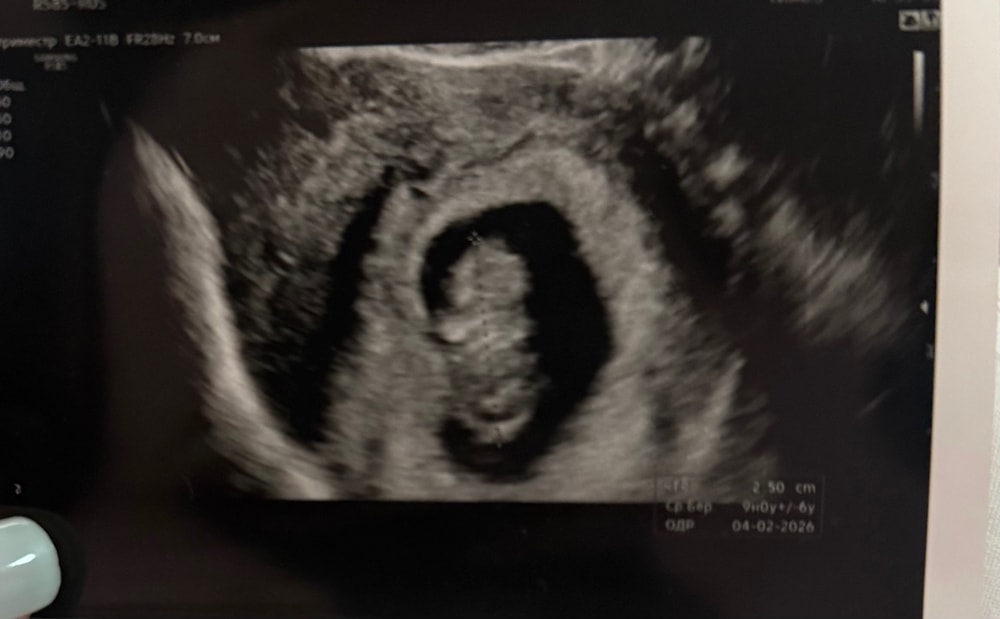

УЗИ

УЗИ, КТГ, доплерСегодня наконец-то сделали узи…и я выдохнула.Сердечко бьется 180 ударов в минуту,за неделю +0,5 мм по КТР.Уже начинаем походить на куколку🥺Но переживаю,что опять ставят 9 недель,хотя по календарю сегодня ровно 10 недель показывает.Врач сказала не переживать.Небольшая угроза все же есть-тонус матки,поэтому остаюсь в больнице.Но уже рада,что с малышом все хорошо.Надеюсь и дальше будет так🙏🏻